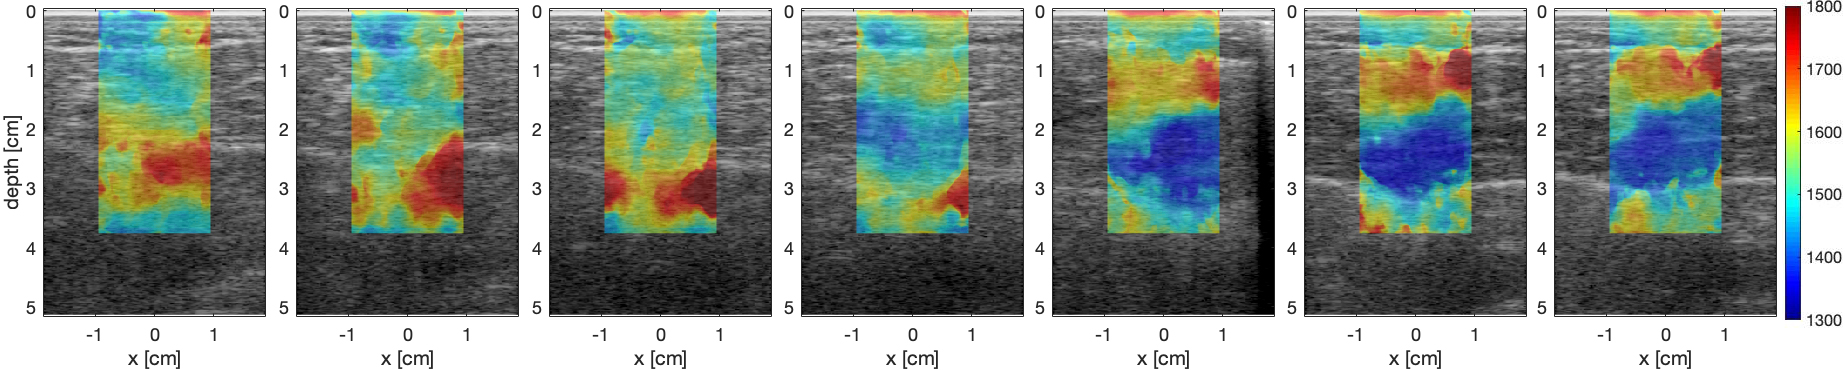

Fig. 4: Results for a squat maneuver. (a) shows the results for the transition from standing (left) to crouching (right) and (b) for the transition from crouching to standing position. Fig. 1(a) shows the location of the muscles in the frame. Blue denotes lower sound speeds, correlated with relaxed muscles, red denotes higher sound speeds, correlated with contracted muscles. Both cases show that the soleus (inside of the leg - bottom of the image) is doing most of the work in the crouching position while the gastrocnemius (outside of the leg - top of the image) is doing most of the work in the standing position.

Our experimental results are presented in Fig. 3, with Fig. 3(a) showing the response for the transition from standing to crouching (down phase) and Fig. 3(b) for the transition from crouching to standing. Red color denotes higher sound speeds that correlate with contracted muscle, while blue color denotes lower sound speeds, that correlate with relaxed muscle.

Results in both cases match the expected action. In the down phase, we see the task start with the GC (outside of the leg / top part of the image) with the soleus starting to activate on the third frame, and slowly transition to the soleus, where we see that the GS slowly relaxes and the soleus slowly contracts. On the up phase, we see the complementary behavior, where the work is initially carried out by the soleus, and slowly transitions to the GC.